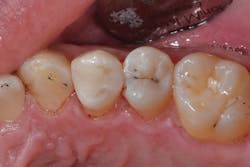

Figure 4: Final restoration on tooth No. 12

After light curing the Prime&Bond Elect for 10 seconds, the composite resin material was placed, occlusion checked, and the restoration completed (figure 4). Six months later, the patient returned for a hygiene recall appointment and reported no negative postoperative sequelae with the restoration on tooth No. 12. Bitewing radiographs were taken as a part of the exam. Not only did the restoration show excellent adaptation to the internal cavity walls, but no voids or black lines indicative of a thick adhesive layer were present (figure 5).